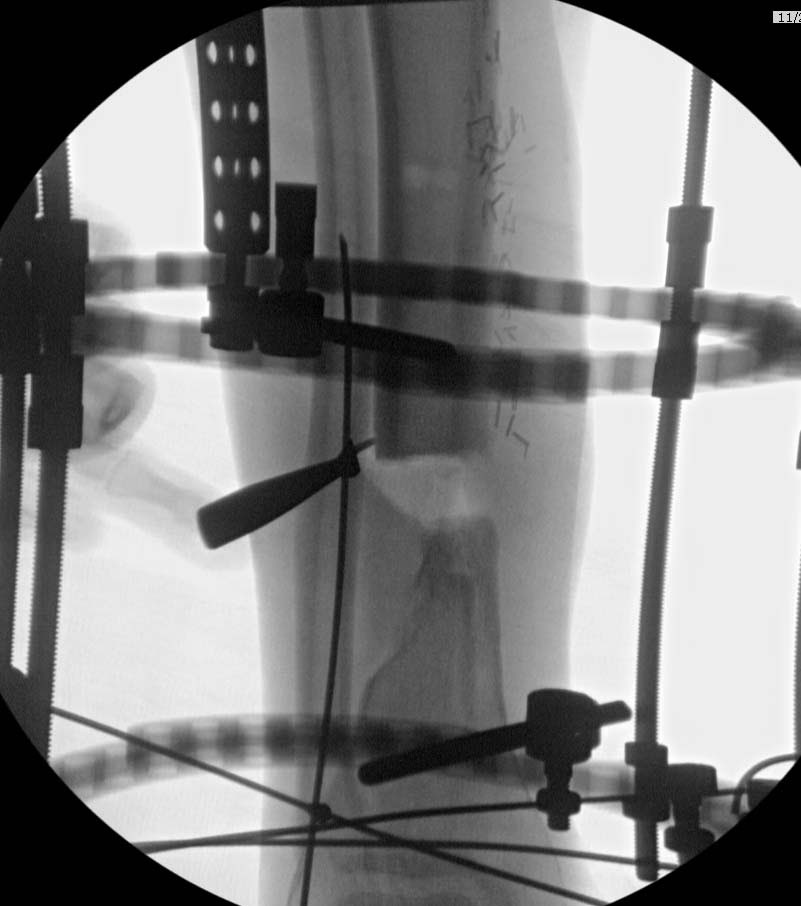

Здравствуйте уважаемые коллеги, прошу поделиться опытом лечения подобных повреждений-осложнений. Пациент Б. 40 лет, поступил в клинику 6.11.19 с огнестрельным переломом н/3 правого бедра и повреждением магистральных сосудов. Произведена ПХО ран, стабилизация перелома(с укорочением на 5 см.)стержневым АВФ, шов сосудов конец в конец. К сожалению, неверная выжидательная тактика привела к нагноению раны(Kl.pneumoniae).22.11.19 Этапная ХО раны, перемонтаж АВФ по типу-гибрид, удаление девитализированных костных фрагментов, депонирование дефекта бусами-спейсерами (амикацин-ванкомицин),VAC, Тигацил 100 мг.сут.26.11, 29.11, 3.12-этапные ХО с заменой бус и VAC,бак.посевы(возбудитель присутствует) . Макроскопически рана очистилась, гранулирует, однако имеется воспаление вокруг стержней. t. тела-в пределах нормы, лейкоциты снизились с 9,5 до 6.3, СОЭ с 62 до 31,СРБ с 98 до 49,гемогробин-98.Какую тактику применить на данном этапе?1 Masquelet с конверсией на гвоздь(пластину) с антибиотиком.2Аппаратное лечение с транспортом кости.3Другие возможные варианты.Заранее благодарю за помощь.

Судя по снимкам, дистальный отломок недостаточно фиксирован. Лучше ввести лишние спицы, потом удалить, чем каждый раз возвращаться к хирургической обработке. АПВФ - не работает, дистальный отломок, вместе с голенью - болтается. Надеяться на стержень с АБ покрытием - опрометчиво, на фоне вторичной инфекции - не поможет.

Воспаление в области стержней аппарата по причине:1. Инфекция идет по медуллярному каналу. 2. Нестабильность аппарата (механическая резорбция).

А воспаление вокруг стержней происходит из-за того, что на бедре мягкие ткани более мобильные, и возле нестабильных стержней образуется реактивное воспаление. Если не лечить, тогда воспаление может перейти в глубокие слои, а в данном случае (fat necrosis), т.е. локальный некроз, который лечится обработкой и созданием стабильности.